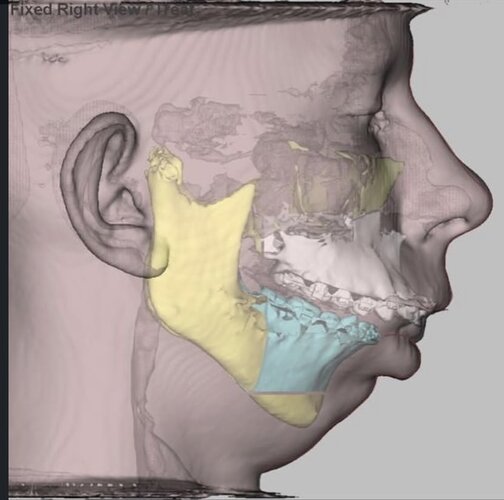

Fucking insane this is anatomically possible lol. Looks good though.

3 whole centimetres on the lower jaw is insane, maybe it’s not over for some of you. Just gotta find a surgeon willing to do such movements.

The amount of upper jaw movement is unclear from what the surgeon has said, but it isn’t massive as seen by the scans and the fact that the patient’s upper lip has not been chimpified.